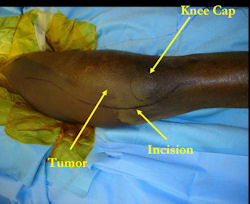

Surgery

Examples of radical limb sparing surgeries for osteosarcomas in various anatomic locations (distal femur, proximal tibia, proximal humerus, scapula)

In each case, the tumor and bone from which it arose were resected. This required meticulous dissection, mobilization and preservation of adjacent pertinent neurovascular structures. In each case presented here, the defect was reconstructed with a special modular segmental tumor prosthesis. This also replaces the adjacent joint in many instances.

| Proximal Tibia Osteosarcoma: Limb-Sparing Surgery |

Intraoperative photos